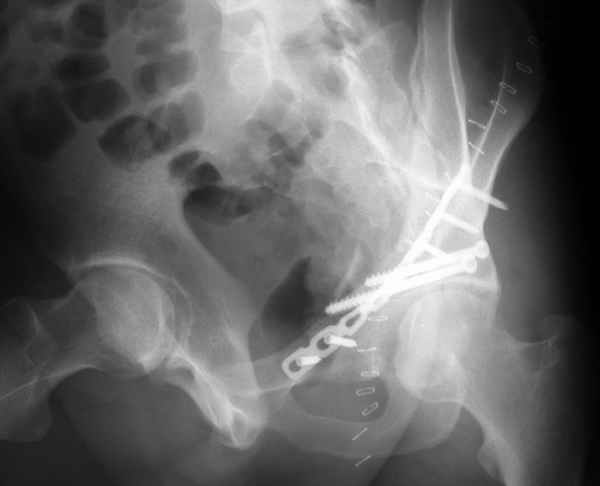

Повреждение сложное. DS:Ротационно нестабильное повреждение таза, перелом боковой массы крестца,ипсилатеральный высокий двухколонный перелом вертлужной впадины с центральным смещением сустава, двусторонний перелом лонных и седалищных костей.

При оперативном лечении прогноз относительно благоприятный. Показано два доступа - чрезвертельный Y-образный и затем синтез лонных костей двумя пластинами.

Разрушения оказались более обширные чем видно ра рентгенограмме. Только пять фрагментов с суставной поверхностью, два почти свободных. Послеоперационная картинка в цифре отсутствует, да она и не очень красивая. Удалось собрать суставную поверхность, много осколков без хряща на передне внутренней поверхности остались сами по себе, передние отделы теза синтезировал. Против обыкновения оставил больную на вытяжении.